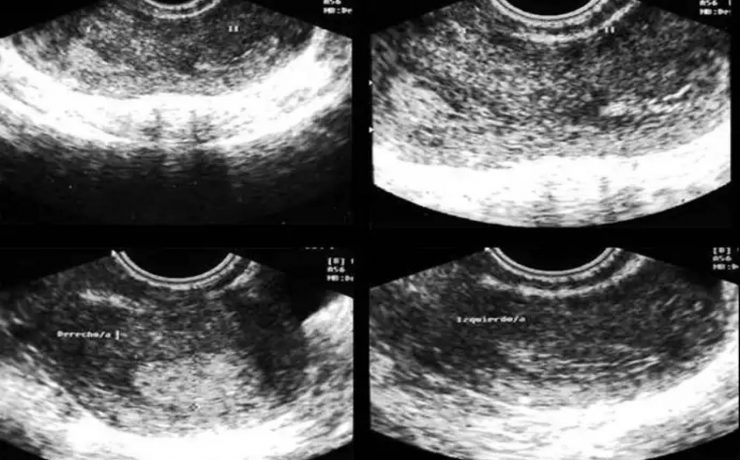

El parénquima esplénico tiene una ecogenicidad similar al hígado y menor que el riñón adyacente. Su valoración ecográfica es útil para confirmar la esplenomegalia y en el estudio de las lesiones esplénicas focales y de los traumatismos abdominales. El aumento del tamaño del bazo, que puede ser difícil de valorar